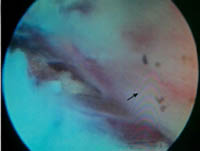

术中所取出的髓核组织 术中所看到的神经根